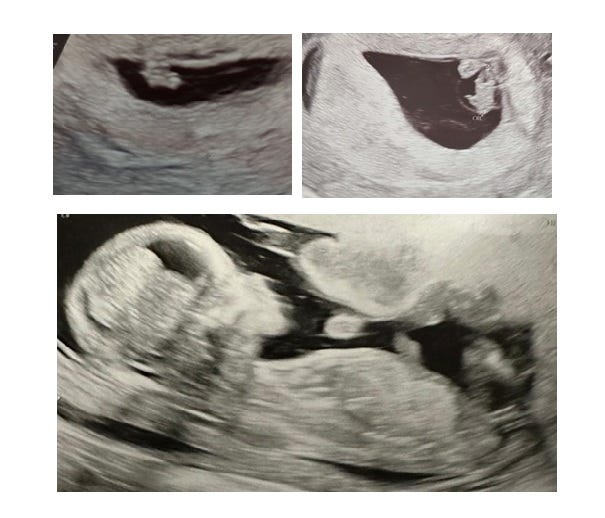

You gave us a couple of weeks’ excitement before throwing hurdle one at us. The most traumatic moment of mine and Daddy’s life arrived shortly after, when I woke up (from a dream about losing you, nonetheless) in a pool of blood. But we established that rather than you leaving us, my body was expelling – we’ll never know – but possibly an inviable twin. You, on the other hand, were clinging on for dear life. The most beautiful fuzzy blob on a screen I have ever seen.